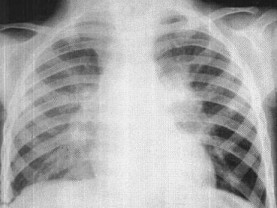

女,3岁,低热、咳嗽2月余,结合胸片,最可能的诊断为()

• A.原发综合征

• B.肺门淋巴结核

• C.淋巴瘤

• D.支原体肺炎

• E.间质性肺炎